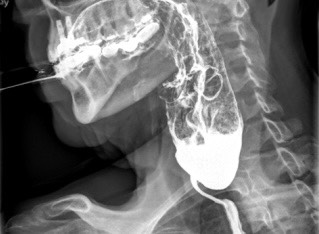

Fue valorada por ORL, que descartó lesiones estructurales relevantes, aunque observó retención de saliva en senos piriformes. La endoscopia digestiva alta reveló estenosis esofágica a nivel cricofaríngeo, con dificultad para el paso del endoscopio y desgarro mucoso incidental, con biopsias esofágicas sin alteraciones. Se realizó un TAC que descartaba compresión extrínseca. El estudio esófago-gastroduodenal (EGD) con videofluoroscopia mostró una gran dilatación faríngea con restos alimentarios retenidos en senos piriformes secundaria a estenosis de contornos regulares en la transición faringo-esofágica de 2,6 cm (Figura 1).

Figura 1. - Videofluoroscopia evidenciando una gran dilatación faríngea con restos alimentarios retenidos en senos piriformes y estenosis de contornos regulares en la transición faringo-esofágica de 2,6 cm sugerente de impronta del músculo cricofaríngeo.